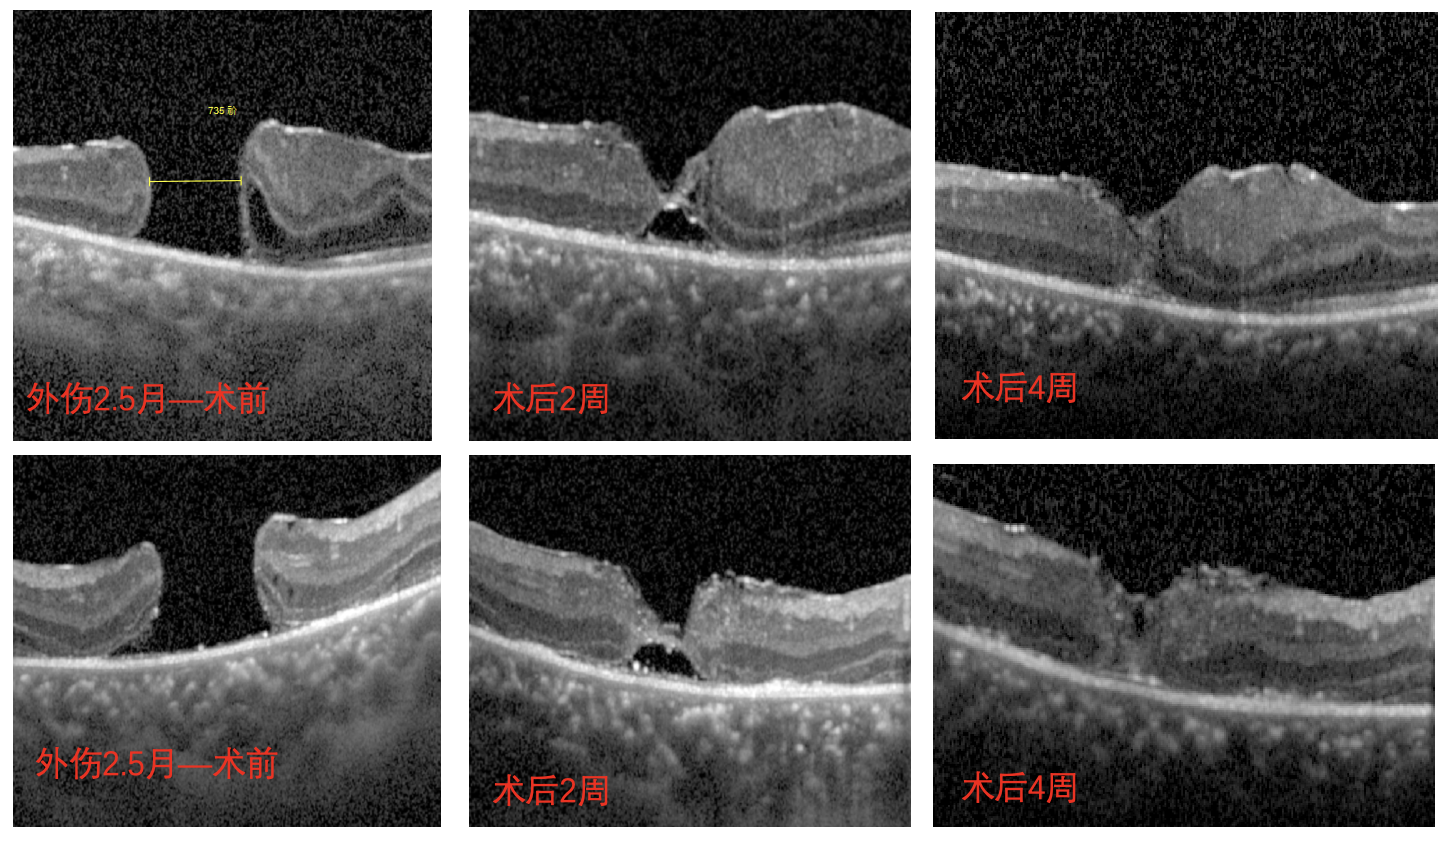

但術(shù)后一個(gè)月復(fù)查時(shí)發(fā)現(xiàn),南南的眼底恢復(fù)情況并不好,檢查時(shí)還可見(jiàn)黃斑處的裂孔,并且裂孔越來(lái)越大,演變成難治性黃斑裂孔。

經(jīng)過(guò)完善的術(shù)前檢查和評(píng)估后,李海波博士后用創(chuàng)新術(shù)式——剝除黃斑裂孔周邊殘余的內(nèi)界膜組織,通過(guò)利用黏彈劑固定翻轉(zhuǎn)的內(nèi)界膜瓣為南南進(jìn)行治療。術(shù)后24小時(shí)復(fù)查時(shí),南南黃斑處的裂孔已實(shí)現(xiàn)愈合,視力也得到了明顯的改善,現(xiàn)已康復(fù)出院。